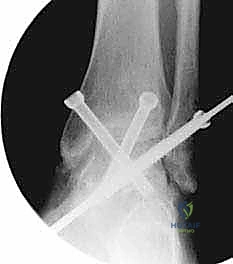

- التصوير المقطعي المحوسب (CT Scan): إجراء بالغ الأهمية قبل الجراحة. يوفر صوراً ثلاثية الأبعاد للعظام، مما يساعد الدكتور هطيف في تقييم جودة العظم بدقة، تحديد حجم التكيسات العظمية، والتخطيط الهندسي الدقيق لزوايا إدخال البراغي الجراحية.

هو إحداث توازن مثالي بين الجراحة المفتوحة وجراحة المناظير. يقوم الأستاذ الدكتور محمد هطيف بإجراء الجراحة عبر شقين أو ثلاثة شقوق صغيرة جداً (لا تتجاوز 2-4 سم). من خلال هذه النوافذ الصغيرة، وباستخدام أدوات جراحية دقيقة ومخصصة، يتمكن من الرؤية المباشرة للمفصل، وإزالة الغضاريف التالفة بالكامل، وتجهيز العظام للدمج، ثم تثبيتها بالبراغي.